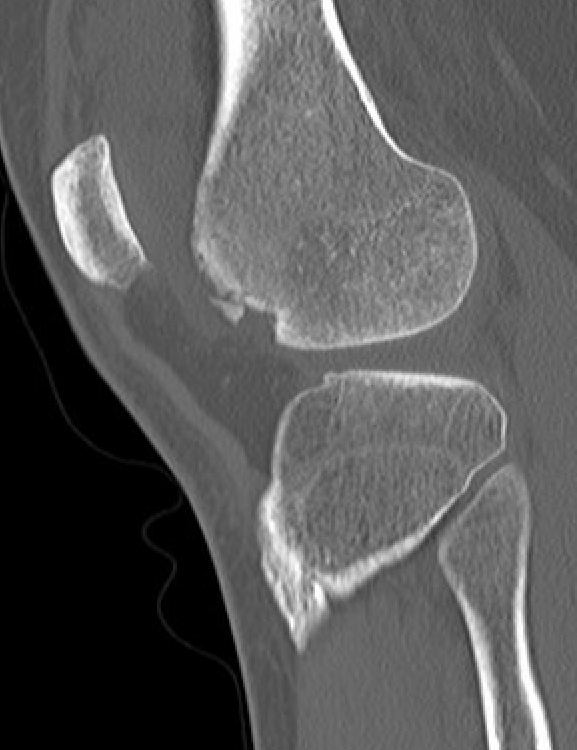

CT

Osteochondral fracture of the lateral femoral condyle

Large osteochondral fracture medial facet patella

Large osteochondral fracture lateral femoral condyle